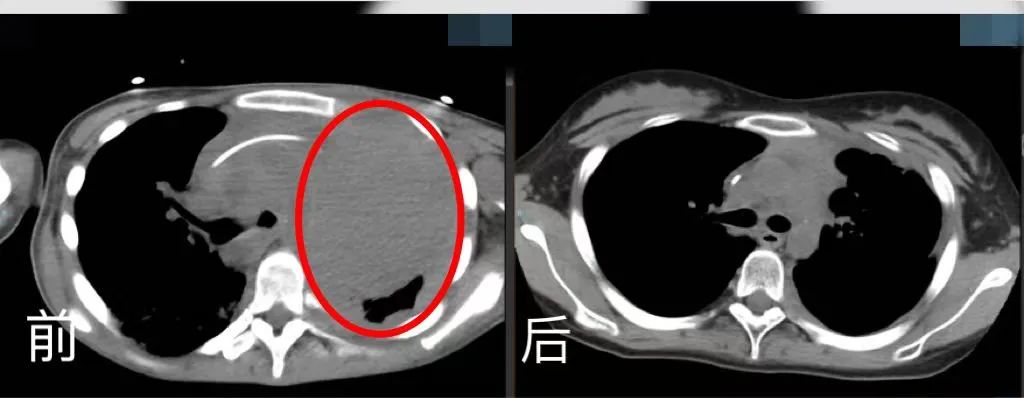

時(shí)間回溯到2022年2月,16歲的小玉因咳嗽、咳痰及咯血前往家鄉(xiāng)的醫(yī)院就診,隨后被診斷為原發(fā)縱膈大B淋巴瘤。由于腫瘤體積大,對(duì)縱膈的大血管及心臟產(chǎn)生壓迫,情況十分危急,并且腫瘤已經(jīng)侵入肺部及骨髓,病情已是晚期。

在經(jīng)過(guò)標(biāo)準(zhǔn)的一線治療后,腫瘤消退并不理想,隨后的靶向免疫化學(xué)二線、三線、四線治療仍無(wú)法控制病情的惡化。經(jīng)過(guò)多次抗腫瘤治療,小玉的身體每況愈下、免疫功能逐漸被摧毀,加之肺部病灶大,并發(fā)嚴(yán)重的肺部感染且無(wú)法進(jìn)食,體重快速下降至30公斤左右,被多位醫(yī)生判定為臨終狀態(tài),幾乎無(wú)救治可能。

胸腔CT前后對(duì)比。四川省腫瘤醫(yī)院供圖

2023年1月,曙光出現(xiàn)——小玉胸部腫瘤達(dá)到部分緩解,從ICU轉(zhuǎn)入綜合(特需)科。

經(jīng)過(guò)2周的院內(nèi)嚴(yán)密監(jiān)測(cè)護(hù)理,小玉沒(méi)有發(fā)生細(xì)胞因子釋放綜合征和神經(jīng)相關(guān)毒性等不良反應(yīng),再次復(fù)查影像學(xué)病灶幾乎完全消失。